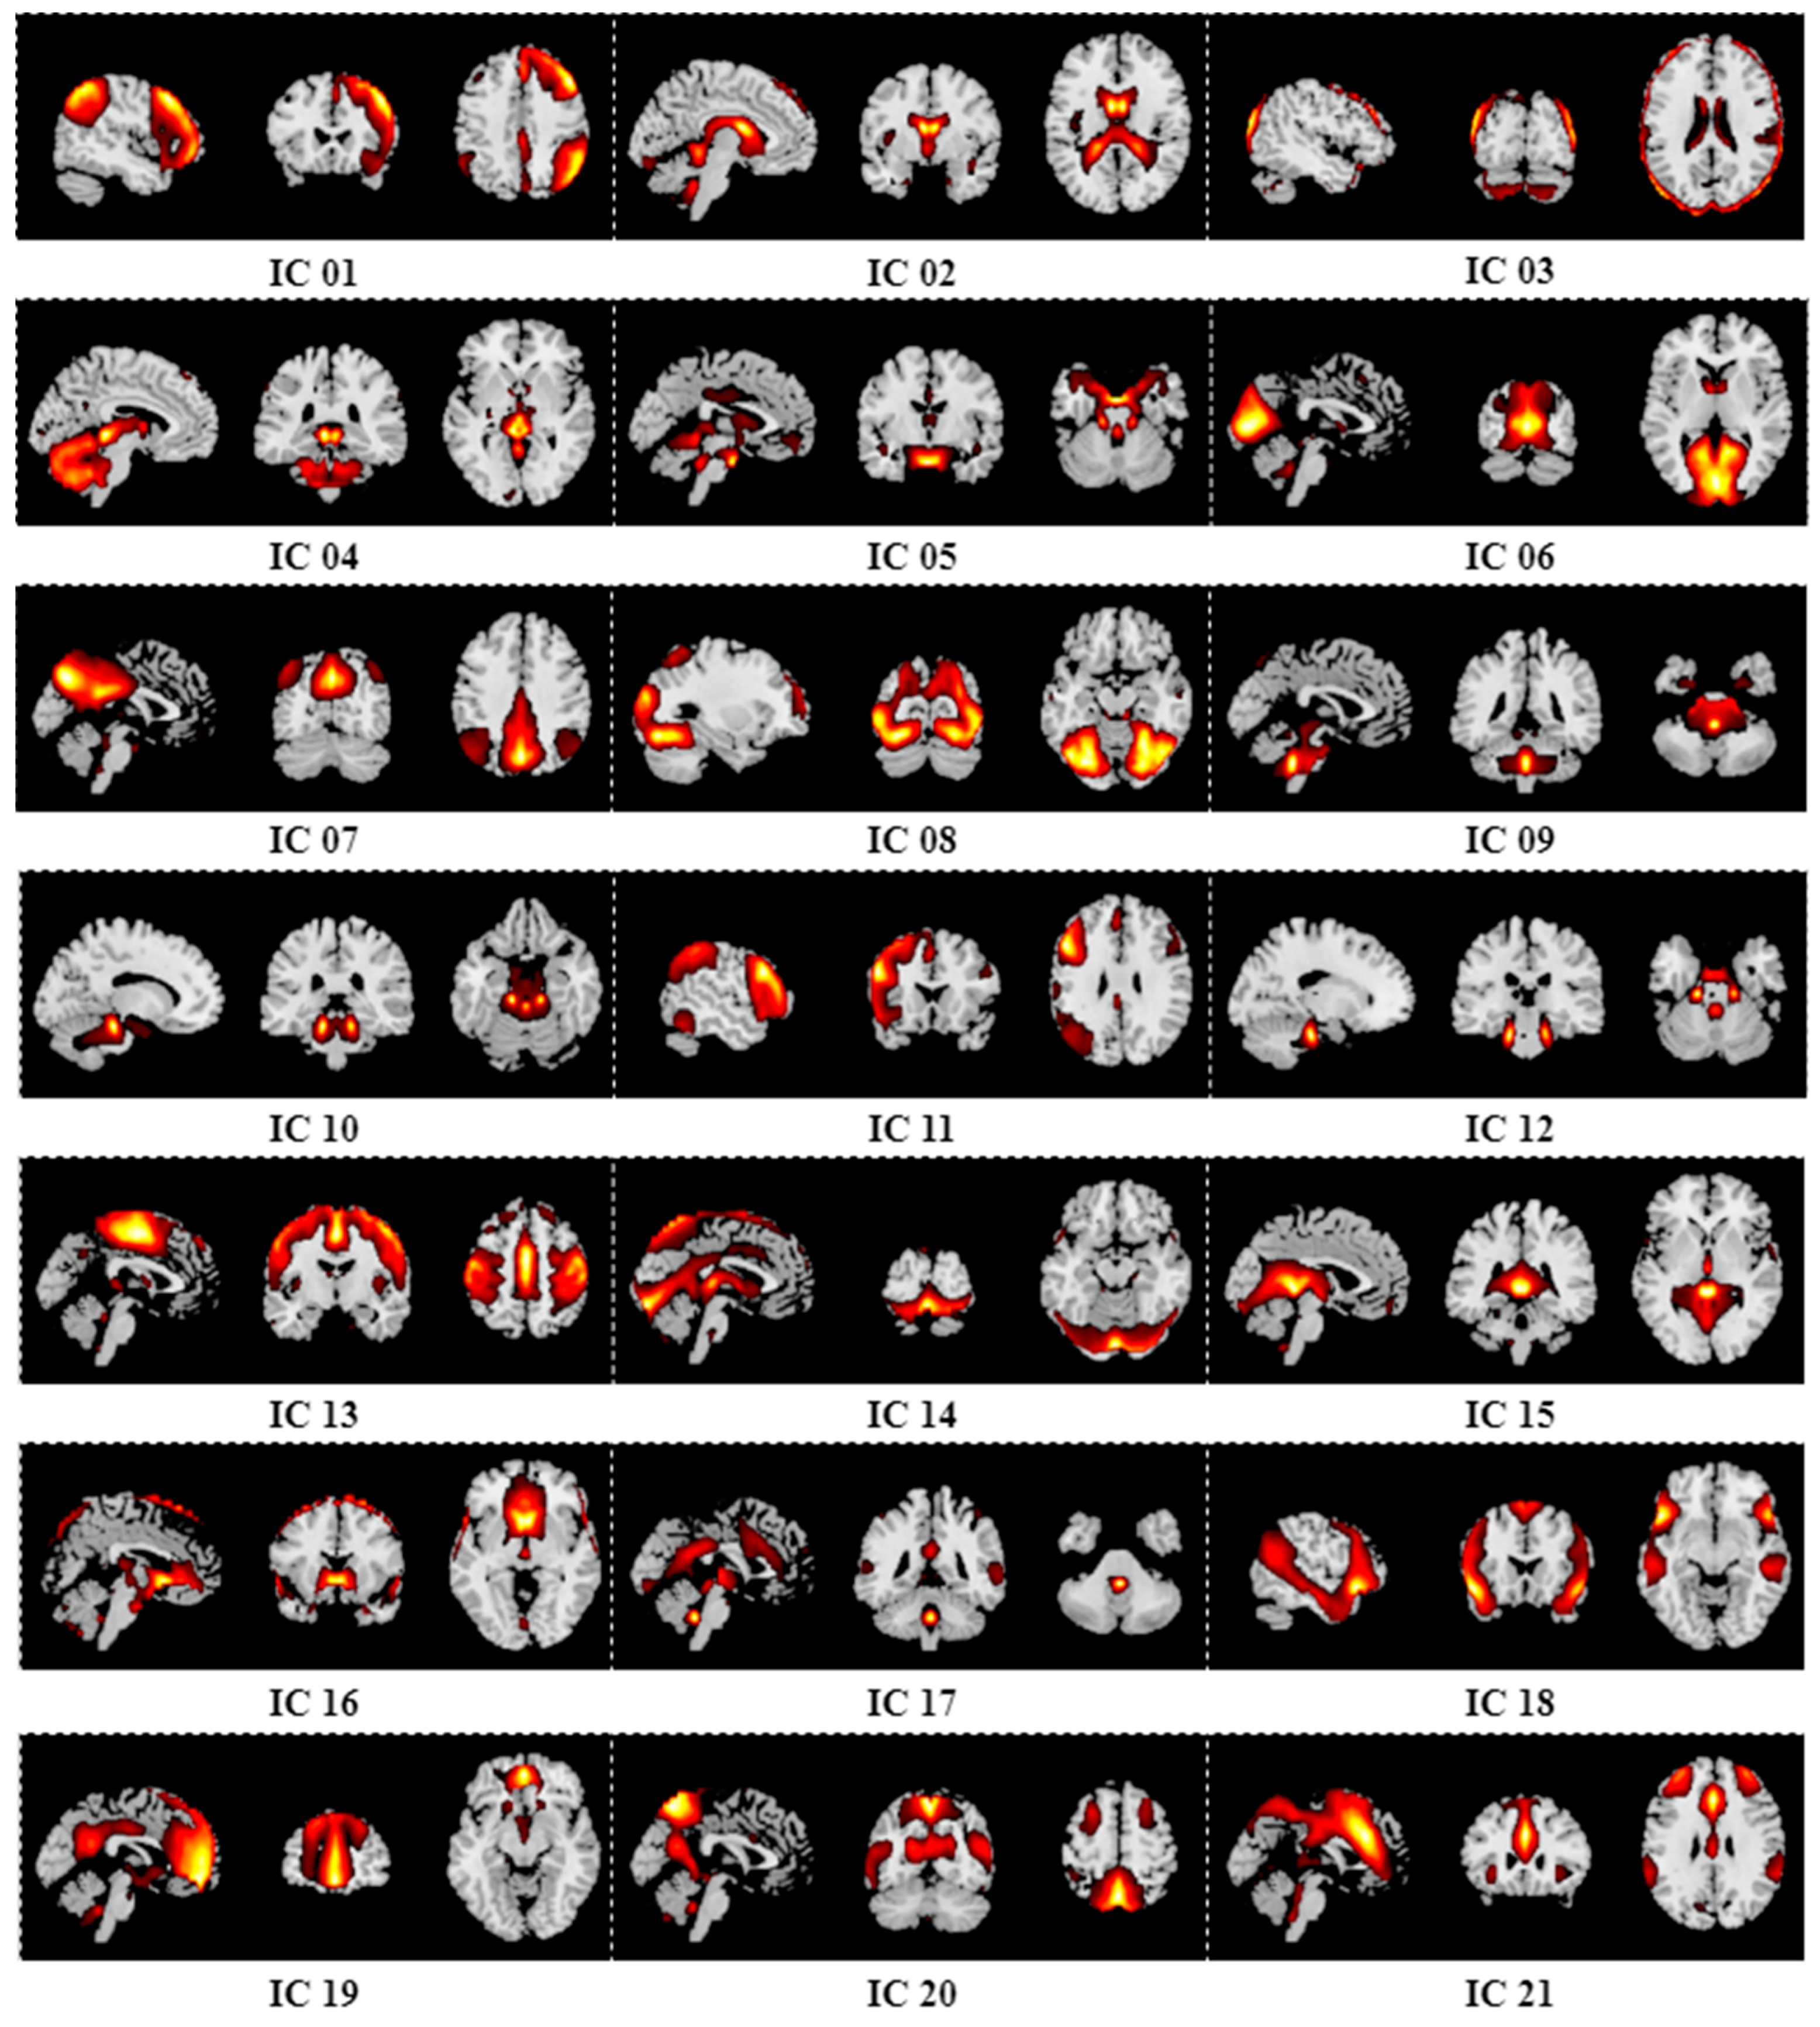

Appendix B. Results of Group ICA

| 27 | 69.52% | 81.15% | 73.71% | 66.61% |